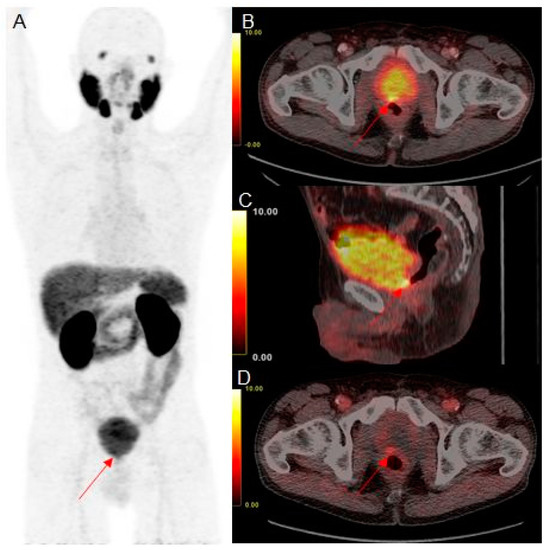

However, additional early static PET scans yielded a lower number of equivocal findings and improved characterization of equivocal findings in scans 60 min p.i., as demonstrated in Figure 1.

Figure 1. Example of an equivocal finding in the prostate fossa in 68Ga-PSMA-11 PET/CT scans 60 min p.i. with maximum intensity projection (A), fused axial (B), and fused sagittal (C) slices, and positive findings in the early fused axial (D) slices of a prostate cancer patient with biochemical recurrence after radical prostatectomy and salvage radiation therapy (PSA, 0.46 ng/mL). Intense focal uptake is the present paramedian at the posterior surface of the urinary bladder (red arrowhead). A clear distinction between local recurrence and urinary activity within the bladder is not possible in late images (SUVmax of focal uptake, 8.9; SUVmax of urinary bladder, 8.9). However, focal tracer accumulation is clearly visible in the early images (SUVmax of focal uptake, 3.3; SUVmax of urinary bladder, 2.7).